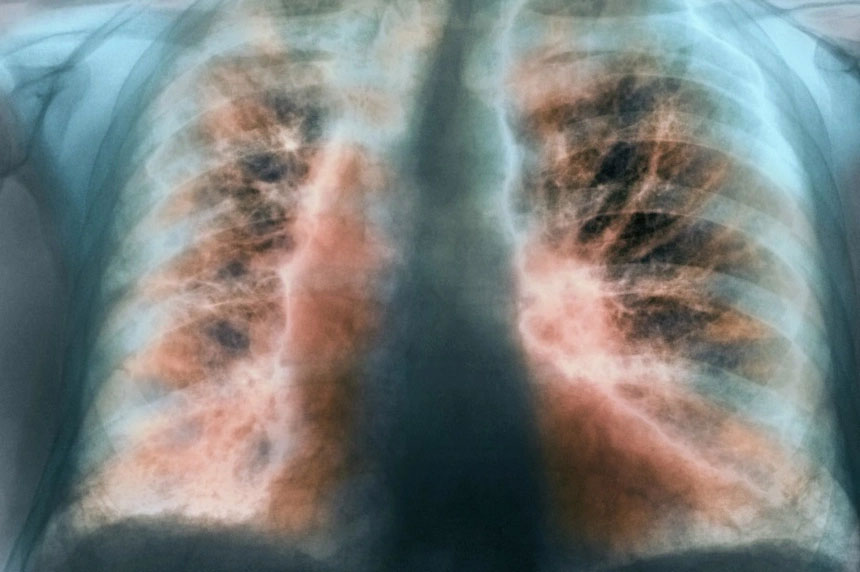

Xơ phổi hậu Covid-19 có thể hồi phục sau một năm. Ảnh: Freepik.

Hình ảnh tổn thương xơ hóa giai đoạn sớm và giảm chức năng phổi có thể xuất hiện ở mọi bệnh nhân bị viêm phổi do SARS-CoV-2.

Trên phim chụp CT scan ngực, hình ảnh xơ hóa phổi biểu hiện dưới nhiều dạng và mức độ khác nhau như dải xơ, dày các vách liên tiểu thùy, dạng lưới, giãn phế quản co kéo, phổi có hình tổ ong… Họ cũng có thể bị giảm thể tích phổi ở nhiều mức độ. Khi sinh thiết phổi, hình ảnh sẽ cho thấy tăng sinh tế bào tạo sợi và lắng đọng collagen trên mô bệnh học.